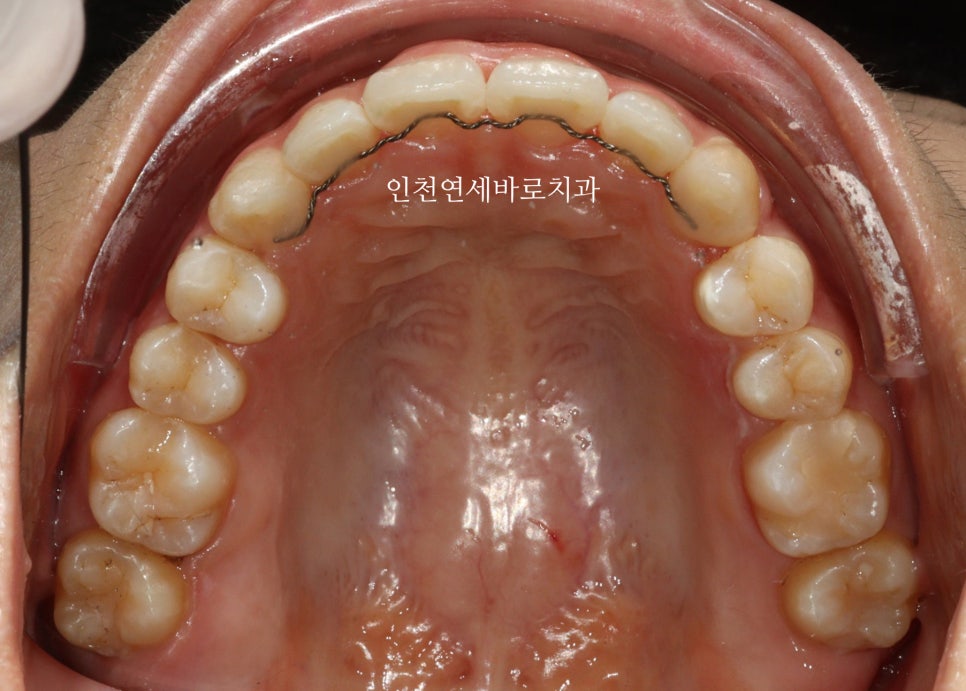

2024년 10월 – 치료 완료

2월초부터 장치를 착용했고 10월에 마무리 했습니다.

1개의 장치를 7일씩 착용하고, 중간에 재제작 한달이라는 기간이 포함된 기간입니다.

치료 전후 비교

전후 비교입니다

전 후 교합의 비교입니다.

안정적으로 교합이 형성되었습니다